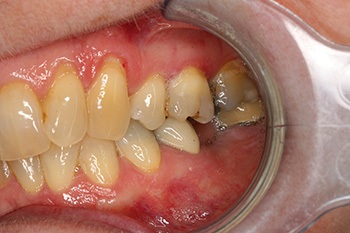

Figs. 8–10: Fifteen years after restoration.

Well, Frances moved to the other side of the country, but I used to see her initially once a year and then every two years, free of charge, just so I could post updates of the case to Dentaltown. As you can see from the most current X-rays, not only has the implant survived, but the bone around the implant (what many worried would be overloaded and lost) looks even better in 2024 than it did in 2009 when the implant was first restored!

One might expect the loading of the bone around a short implant supporting both a molar and a premolar restoration to be really quite high. Classic teaching suggests bone responds to overload by resorbing. But the bone around this implant looks even better after 15 years of overload than it did when it was first restored.

Perhaps we expect too little of the bone around implants. Perhaps, just like muscle, bone responds to loading by becoming stronger, which explains why Frances’ implant X-ray shows better bone levels after 15 years.